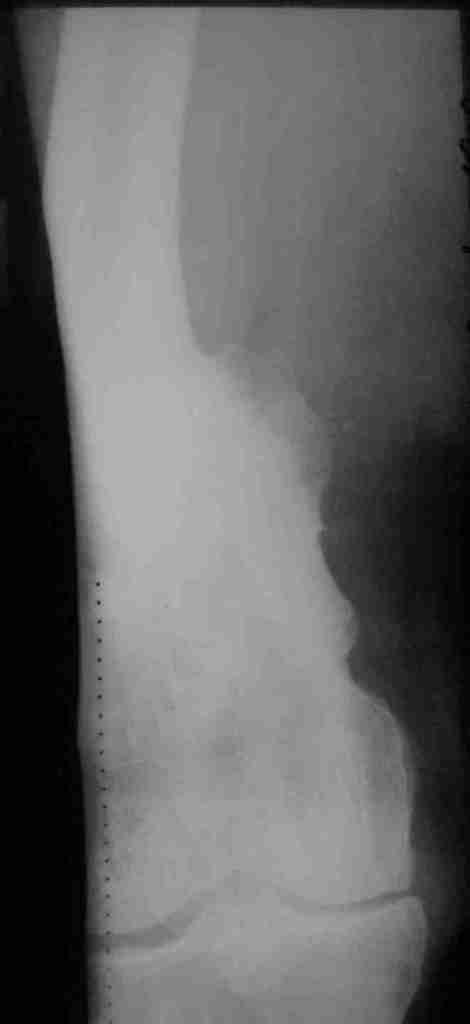

Уважаемые коллеги! Прошу вас принят участие в корректировке алгоритма

действий.

Пациент 69 лет. лечился по поводу перелома н/3 левого бедрамного лет

назад: несостоятельность внутреннего синтеза - АВф- хр. остеомиелит,

свищевая форма с периодическими рецидивами. Результат - укорочение

левого бедра 8 см.

В приложении рентгенограммы и внешний вид бедра.